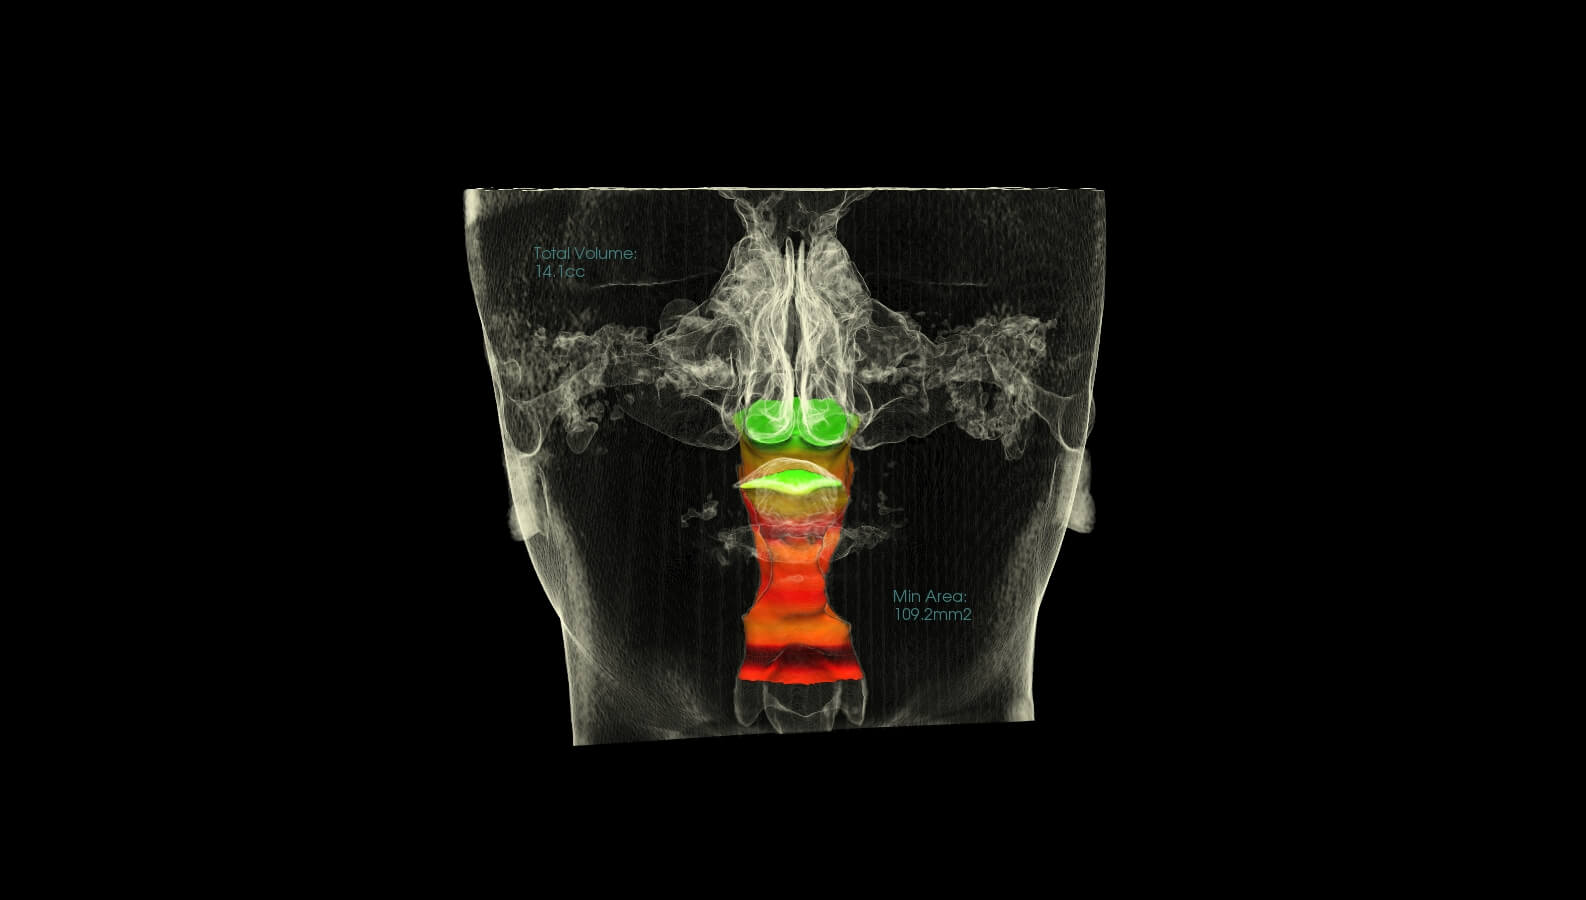

These are before and after CBCT images of patients treated at Marlo A. Miller, DDS. Both struggled with enlarged adenoids and tonsils. An adenotonsillectomy, or removal of the tonsils, was performed based on Dr. Miller and an ENT recommendation. This procedure alleviates airway restriction contributing to breathing/sleep issues and reduced overall health and wellness. Dr. Miller also did some minor Upper and Lower expansion. There is a Significant airway change in both patients, and both report sleeping better and feeling better overall.